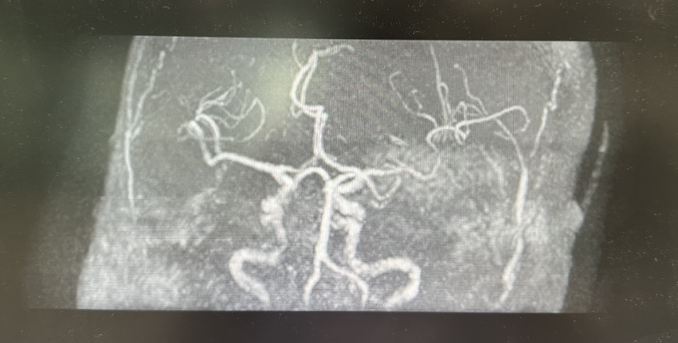

术后48小时查头颅核磁,提示右侧大脑半球大面积脑梗死,右侧大脑中动脉充盈良好。

图四:48小时头颅核磁+血管